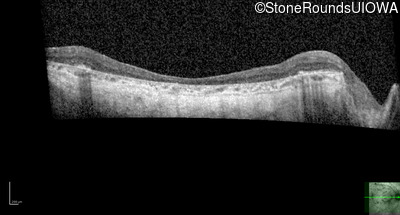

B-Scan Ultrasonography - Right - 20/200 +2

Exemplar